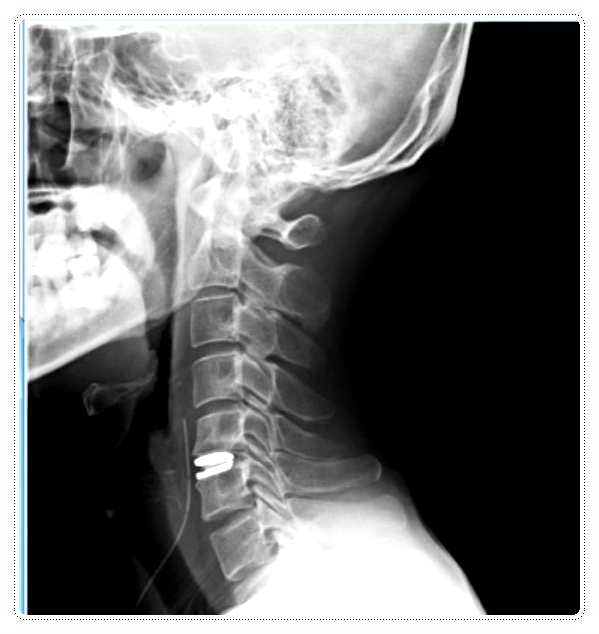

제가 목디스크 치료에서 사용하는 칵스 치료법은 다음과 같습니다.

억지로 밀거나 당기는 방식이 아님

신경 자극을 최소화하면서 관절 가동 범위를 회복

비유하면, 꽉 눌린 스펀지를 서서히 풀어 원래 탄성을 되찾게 하는 과정과 같습니다.

강한 힘으로 통증을 참게 하지 않고, 신경을 자극하지 않는 범위 내에서 이완과 순환을 회복시키는 방식입니다.